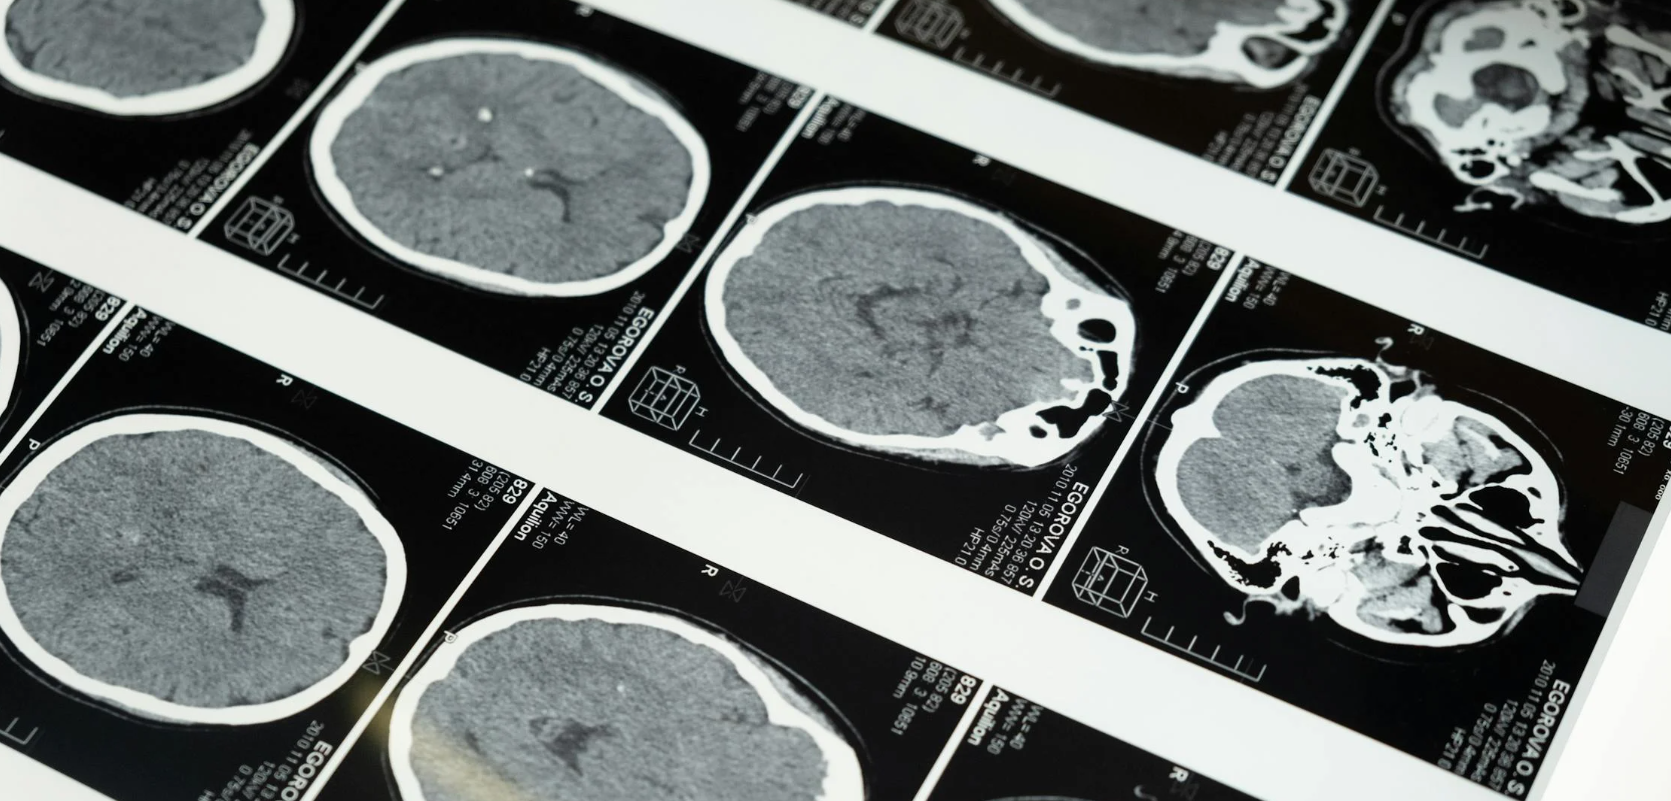

뇌졸중과 뇌출혈은 모두 급성 뇌혈관 질환에 속하지만, 그 증상의 양상에서 미묘한 차이가 존재합니다. 갑작스러운 마비 거나 의식저하에 따라 다릅니다. 뇌졸중은 보통 뇌경색을 의미하며, 뇌혈관이 막히면서 산소와 영양 공급이 차단되어 뇌세포가 손상되는 질환입니다. 반면, 뇌출혈은 뇌혈관이 터져 뇌 안에 출혈이 발생하는 경우를 말합니다. 뇌졸중의 가장 흔한 초기 증상은 편측마비, 즉 신체 한쪽의 갑작스러운 마비입니다. 손이나 다리에 힘이 빠지고, 입이 한쪽으로 틀어지거나 말을 제대로 하지 못하는 언어장애, 시야의 변화가 동반됩니다. 뇌졸중의 증상은 대체로 점진적으로 나타나지만, 증상이 시작된 후 수 분에서 수 시간 안에 악화될 수 있습니다. 반면, 뇌출혈은 더 극적으로 증상이 발생합니다. 극심한 두통이 먼저 나타나며, 구토, 어지러움, 의식 저하, 경련 등이 동반되는 경우가 많습니다. 뇌 속으로 피가 퍼지기 때문에 뇌압이 상승하고, 이는 곧 의식을 잃거나 혼수상태에 빠지는 원인이 됩니다. 뇌출혈은 응급처치가 늦으면 사망률이 매우 높기 때문에 즉각적인 조치가 요구됩니다. 이처럼 두 질환 모두 뇌기능 손상을 유발하지만, 뇌졸중은 혈류 차단으로, 뇌출혈은 출혈로 인해 증상이 발생한다는 점에서 차이가 있으며 증상의 성격도 점진적이냐 급격하는지에 따라 구분할 수 있습니다.

뇌졸중과 뇌출혈의 가장 본질적인 차이는 발병 원인입니다. 뇌졸중은 대부분 뇌경색으로, 혈전이나 색전이 뇌혈관을 막아 발생합니다. 이는 고혈압, 고지혈증, 당뇨, 심장질환, 심방세동 등이 주요 원인이며, 잘못된 식습관과 운동 부족, 음주 및 흡연 등 생활습관의 영향도 큽니다. 특히 동맥경화증은 뇌졸중 발생률을 높이는 주요 원인 중 하나입니다. 혈관 벽에 지방이 쌓이면서 혈관 내경이 좁아지고, 작은 혈전이라도 혈류를 완전히 차단할 수 있는 상태가 되기 때문입니다. 뇌졸중은 50대 이상 중장년층에서 많이 발생하지만, 최근에는 스트레스와 과로로 인해 젊은 층에서도 발생률이 증가하고 있습니다. 반면 뇌출혈은 주로 고혈압성 뇌출혈과 외상성 뇌출혈, 그리고 뇌동맥류 파열로 나뉩니다. 고혈압이 오랜 시간 지속되면 혈관 벽이 약해지고, 어느 순간 혈압이 급상승하면 혈관이 파열되어 출혈이 발생합니다. 또한 사고나 낙상으로 두부에 외상이 가해질 경우 뇌혈관이 손상되어 출혈이 생기기도 합니다. 특히 뇌동맥류는 말 그대로 혈관 일부가 풍선처럼 부풀어 오르다가 터지는 것으로, 평소 자각증상이 거의 없지만 파열되면 매우 치명적입니다. 이러한 차이로 인해 뇌졸중은 예방 가능한 생활습관 병에 가깝고, 뇌출혈은 고위험성 돌발에 더 가깝다고 볼 수 있습니다.

뇌졸중과 뇌출혈 모두 예방이 가장 중요합니다. 하지만 그 접근 방식에는 차이가 있습니다. 먼저 뇌졸중의 예방은 철저한 생활습관 관리에 달려 있습니다. 고혈압, 고지혈증, 당뇨, 비만 등의 기저질환을 조절하고, 짠 음식과 기름진 음식을 줄이며 금연과 금주, 규칙적인 운동을 실천하는 것이 중요합니다. 또한, 혈전 생성 위험을 줄이기 위한 항응고제 복용이 필요할 수 있으며, 특히 심방세동이 있는 환자라면 정기적인 심장 검진과 함께 혈액 응고 상태를 주기적으로 확인해야 합니다. 최근에는 혈관 건강을 체크할 수 있는 앱이나 스마트워치를 활용해 예방적인 관리도 가능합니다. 반면, 뇌출혈의 예방은 무엇보다 고혈압 조절이 핵심입니다. 고혈압이 있더라도 이를 관리하고 꾸준히 약을 복용하면 뇌출혈 위험을 크게 줄일 수 있습니다. 특히 뇌동맥류는 파열되기 전에 MRI, CT, MRA 등으로 조기 진단이 가능합니다. 가족력이 있거나 두통이 자주 발생하는 경우라면 정기적인 뇌혈관 검사를 받아야 합니다. 외상성 뇌출혈을 예방하기 위해서는 낙상 방지가 중요하며, 노년층의 경우 실내 보행 안전장치, 미끄럼 방지 매트 등을 설치하고 운동을 통한 균형감각 향상도 도움이 됩니다. 결국 뇌졸중은 내가

얼마나 건강하게 살고 있느냐에 달려 있고 뇌출혈은 내 몸에 어떤 위험요소가 숨어 있는지를 정기적으로 점검해야 예방할 수 있는 질환입니다. 각자의 생활 패턴과 건강 상태에 맞춰 맞춤형 예방법을 실천하는 것이 바람직합니다.